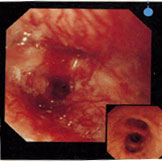

肺がんのレントゲン写真   肺がんの気管支鏡所見

肺癌の気管支鏡所見

(72才男性 1日20本 50年間)

気管支内腔が狭窄している。表面は不整で出血しやすい。 右下は正常者の内視鏡所見